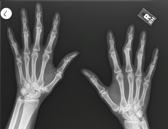

Berta Röntgens Hand 1895

Röntgen Handaufnahme 2005